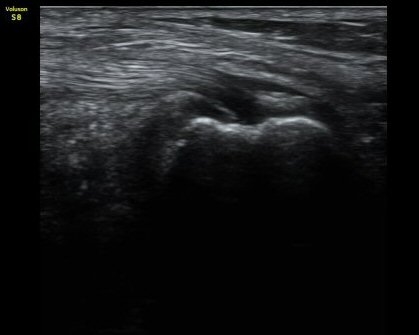

¹«¸­ µÚ ³»Ãø ¹Ý¸·¾çÈûÁÙ(semimembranosusu) Á¾´Ü¸é°Ë»ç¿¡¼­  ÈûÁÙÀÇ ºñÈÄ, ÈûÁ٠ǥÃþÀÇ ¼ö¾×

Àú·ù¿Í ÈûÁÙ ºÎÂøºÎ °æ°ñÀÇ ºÒ±ÔÄ¢ º¯È­°¡ °üÂûµÊ(±×¸² 3).